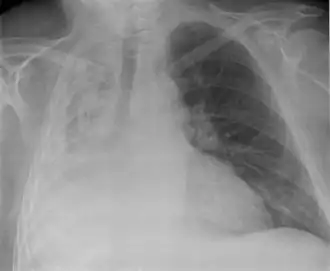

Atelectase of longatelectase is een aandoening waarbij (een deel van) de long geen lucht meer krijgt en daardoor samenvalt (collaps). Atelectase wordt meestal veroorzaakt door een obstructie (afsluiting) van een bronchus, een van de twee hoofdtakken van de trachea (luchtpijp) die rechtstreeks naar de longen leiden.

Ook kleinere luchtwegen kunnen afgesloten raken. Dit kan worden veroorzaakt door een slijmprop, pleuravocht, een geïnhaleerd voorwerp of zelfs door een tumor in de bronchus. De bronchus kan ook worden afgesloten door druk van buitenaf, bijvoorbeeld door een tumor of vergrote lymfeklieren. Wanneer een luchtweg afgesloten raakt, wordt de lucht uit de longblaasjes in het bloed opgenomen, waardoor de alveoli ineenkrimpen. Het ingeklapte longweefsel vult zich meestal met bloed, cellen, serum en slijm en raakt geïnfecteerd.